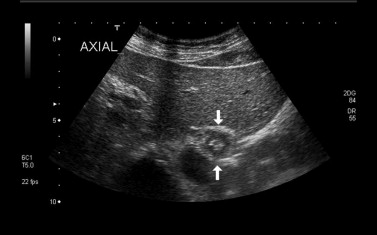

УЗИ не является базовым исследованием для диагностики грыжи пищеводного отверстия диафрагмы, потому что ультразвуковая визуализация ограничена в зоне диафрагмального отверстия из-за наличия воздушных структур и невозможности прямой оценки пищеводно-желудочного перехода. Ультразвуковое исследование при грыже пищеводного отверстия диафрагмы выявляет следующие анатомические признаки:

В серошкальном режиме определяется смещение кардиального отдела желудка через пищеводное отверстие диафрагмы с его появлением в грудной полости.

В серошкальном режиме визуализируется изменение нормальной линии диафрагмы и появление дополнительного эхосигнала выше неё.

В динамическом режиме отмечается изменение положения желудка при дыхательных движениях и натуживании.

В режиме цветового допплеровского картирования возможно выявление сосудистого рисунка стенок желудка в области грыжи.

В энергетическом допплеровском режиме фиксируется изменение кровотока в стенках желудка при нарушении венозного оттока.

В В-режиме определяется деформация пищеводно-желудочного перехода и его неправильное положение относительно диафрагмы.